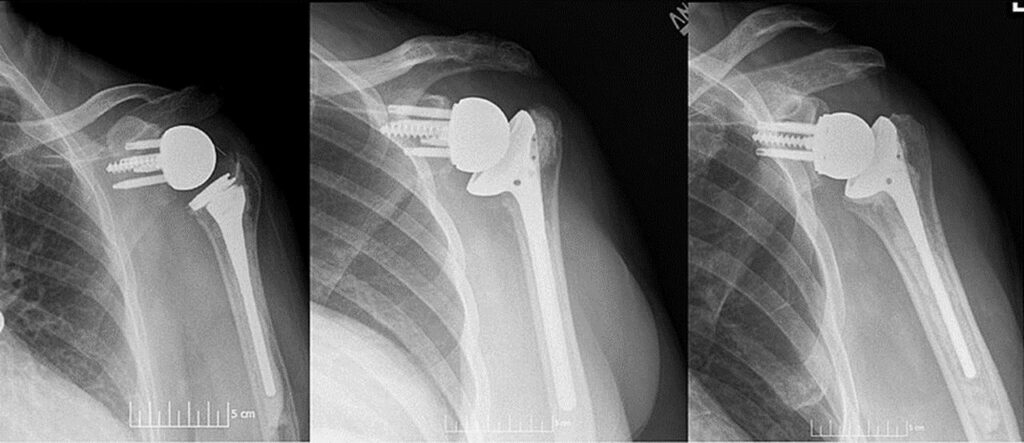

In March 2021, the partnership announced the ProMade Point of Care Center for Complex Orthopedic Solutions (ProMade PoC), the first provider-based 3D design and printing facility for custom complex joint replacement solutions. The facility is physically located at the HSS main facility in New York City, allowing custom patient solutions to be designed and manufactured on-site, reducing wait times and improving patient outcomes due to the high personalization of the devices. Manufacturing engineers and surgeons have a higher level of collaboration than was previously possible. HSS recognizes that the conventional “one size fits all” way of creating implants causes post-operational issues. Custom-made implants reduce these complications, and 3D printing techniques have much more precision in customization than traditional methods.

In March 2022, one year after the ProMade PoC Center was opened, HSS and LimaCorporate announced that the first patient-specific solutions designed there were successfully used in a hip procedure performed by Dr. Robert L. Bully and a shoulder procedure performed by Dr. Patrick Connor. Luigi Ferrari, CEO of LimaCorporate, and Louis A. Shapiro, President and CEO of HSS, expressed pride in the success of these surgeries and of the ProMade PoC center. They are excited about what the future holds for doctors, engineers, and patients with access to such an innovative form of treatment